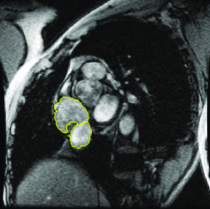

More advanced texture features such as those based on Haar and Gabor filter banks have shown many successes in medical image segmentation (Huang et al., 2005; Malcolm et al., 2007; Santner et al., 2009). Koss et al. (1999) and Frangi et al. (1998) are two works that utilized advanced features to segment abdominal organs and to measure vesselness, respectively. In (Frangi et al., 1998), the eigenvalues of the image Hessian matrix are used for measuring the vesselness of pixels in images. This measure is used for liver vessel segmentation both in a variational framework (Freiman et al., 2009) and in a graph-based framework (Esneault et al., 2010). Statistical overlap prior is another strong appearance prior that has been proposed by Ayed et al. (2009). Their method embeds statistical information (e.g. histogram of intensities) about the overlap between the distributions within the object and the background in a variational image segmentation framework. They used the Bhattacharyya coefficient measuring the amount of overlap between two distributions, i.e. if . Ben Ayed et al. (2009) used this strong prior to segment left ventricle in MR images.